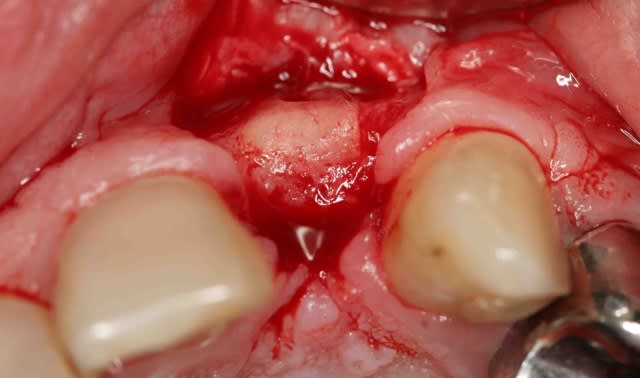

le protocole de Khoury basé sur ses parfaites connaissances du phénomène de cicatrisation permet d'obtenir des greffons de super qualité au moment de la mise en place des implants.

Screenshot015 copie ryteqf - Eugenol

Img 4922 dw6gpg - Eugenol

Img 4924 qsttsv - Eugenol